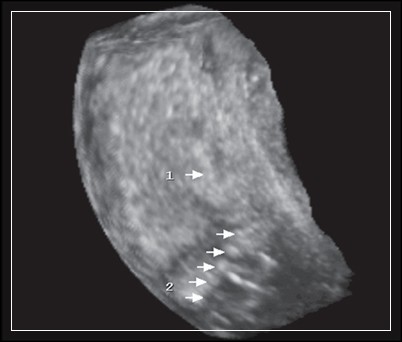

• Ультразвуковые исследования. Для диагностики осложнения применяют трансабдоминальное и трансвагинальное УЗИ органов малого таза, трехмерную эхографию. Определяется высокое стояние дна матки, не соответствующее послеродовому сроку, утолщение ее стенок. Эхография позволяет точно определить наличие инородных тел и остатков последа в маточной полости.